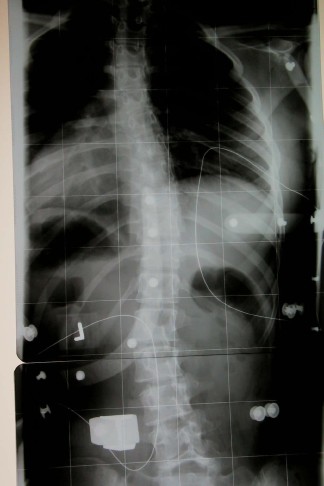

Um mal zu zeigen wie ein hohe Primärkorrektur wirklich aussieht:

- 50° Cobb.o.K.jpg (29.18 KiB) 24077 mal betrachtet

- Im Korsett.jpg (28.78 KiB) 24078 mal betrachtet